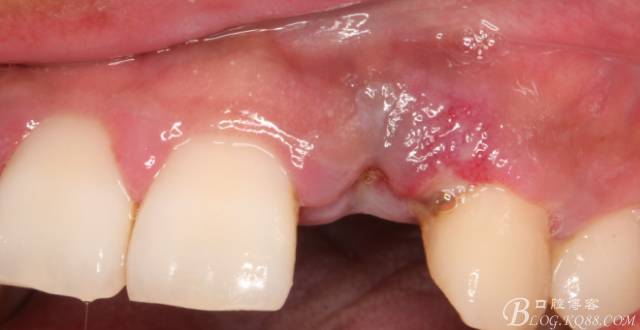

10天拆線一切正常,又過(guò)了兩周患者復(fù)診,自述期間無(wú)異常??趦?nèi)檢查,真的嚇了一跳,唇側(cè)鼓了個(gè)包,擠壓有白色分泌物溢出,絕對(duì)不是膿液,液體排除后,術(shù)區(qū)觸診空虛,外觀塌陷。這時(shí)候考研大夫的時(shí)刻到了,是先觀察一段時(shí)間再說(shuō)?還是馬上進(jìn)行處理?我的回答是:馬上處理!如果你沒(méi)有及時(shí)處理,而是放患者回家觀察,那么接下來(lái)會(huì)發(fā)生如下情況:1.回家后患者家屬及親友會(huì)有很多你可以想象得到的討論;2.患者及家屬會(huì)對(duì)你產(chǎn)生不信任,勢(shì)必會(huì)到其他門診或醫(yī)院檢查,他院大夫會(huì)不會(huì)發(fā)表對(duì)你不利的言論;3甚至?xí)蚁嚓P(guān)法律界人士找你討要說(shuō)法。